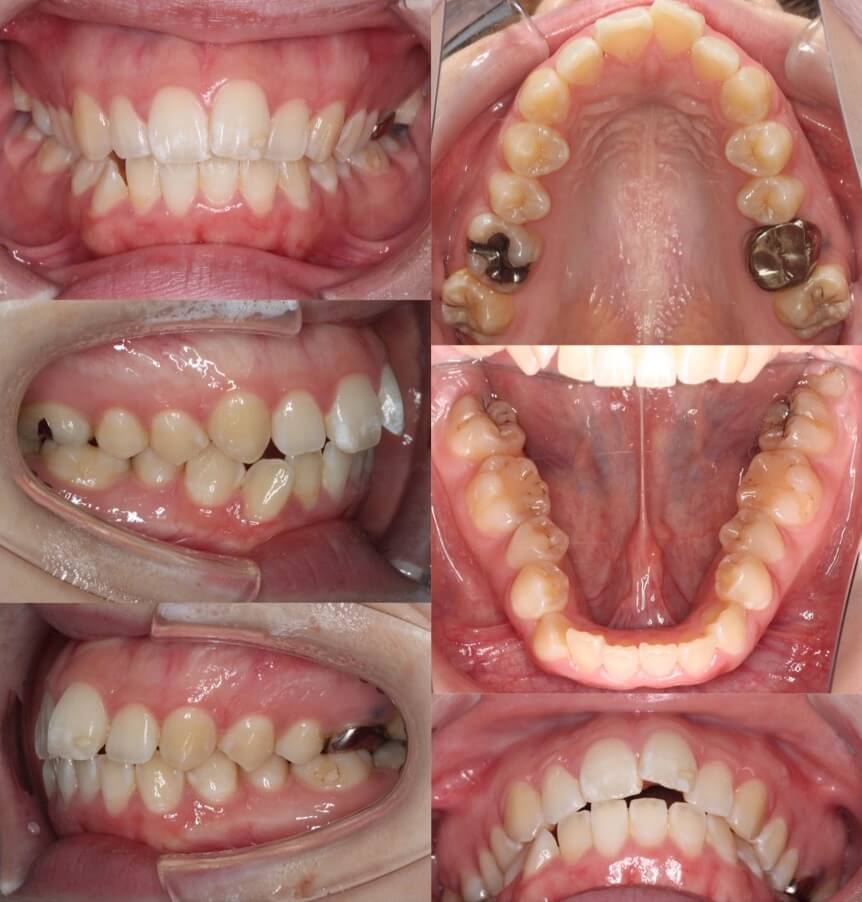

「男性は顔が引き締まる」

高校生男性・唇側矯正装置・下あご後退型

当初は、抜歯矯正治療にするかしないかで、治療方針に迷ったケースですが、最終的には患者さんの希望に沿って抜歯矯正治療にしました。歯の動きがゆっくりであったため、治療期間が3年を超えてしまいました。

<症例概要> 難易度:★★★★☆

主訴:口元の突出・前歯のガタツキ

年齢・性別:高校生男性

住まい:千葉県八千代市市

症状:下顎後退・叢生

治療方針:抜歯空隙の閉鎖(最大固定)

治療装置:唇側矯正装置

固定:歯科矯正用アンカースクリュー(頬側x2)

抜歯:上下第一小臼歯(計4本)

治療期間:3年4か月

リテーナー:上下プレートタイプ+フィックスタイプ

治療費用:968,000(税込)

代表的副作用:痛み・治療後の後戻り・歯根吸収・歯髄壊死・歯肉退縮